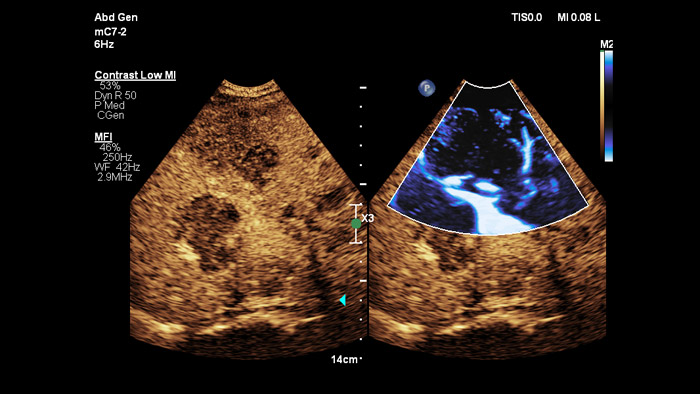

O ElastQ proporciona uma avaliação em tempo real por ondas transversais 2D (2D-SWE) da rigidez dos tecidos não invasiva, reprodutível e fácil de realizar. O ElastQ também inclui a capacidade de efetuar medições retrospetivas em imagens armazenadas e inclui um mapa de confiança para a apresentação adequada da propagação por ondas transversais.

ElastQ imaging